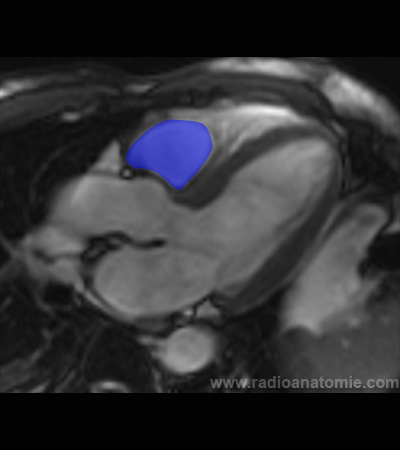

Radioanatomie et plans de coupe en IRM cardiaque

Oreillette gauche